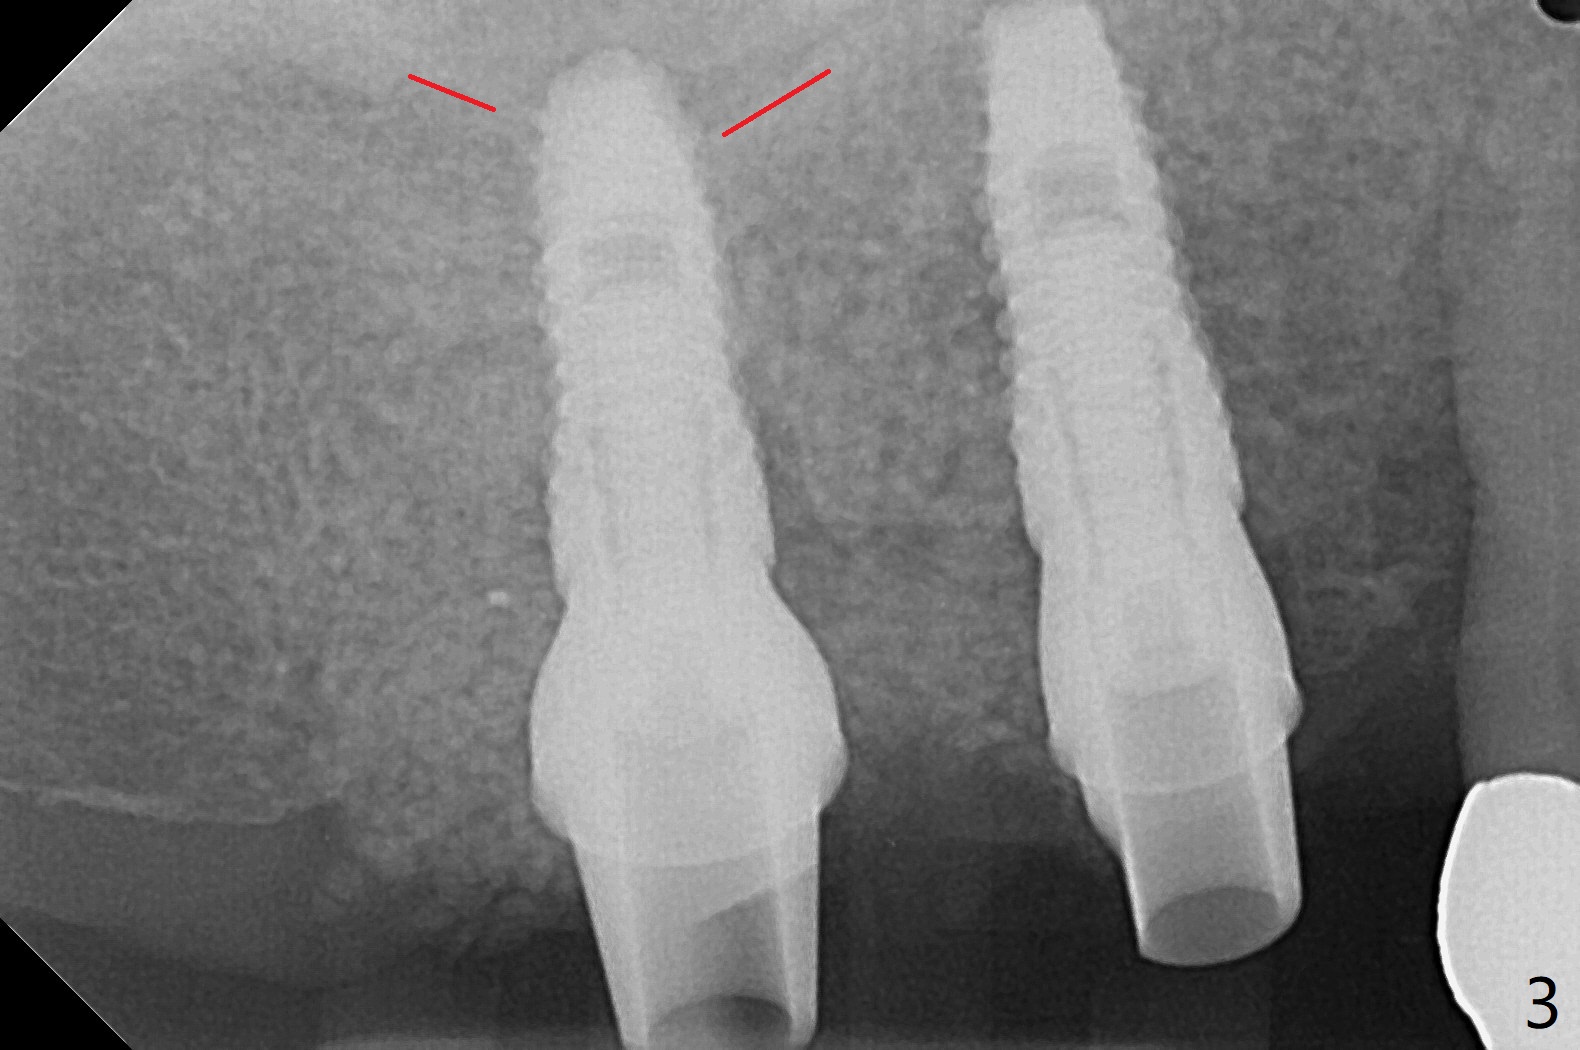

3号牙钻洞后,no-stop fixture driver好像不能完全与植体就位,所以2号牙导板钻洞和种植更不稳定(图一(咬翼片)),安置基台后(3号牙位使用5.5毫米profile drill),放置粘性骨粉(图二),2号牙植体可能穿过窦底(图三:红虚线)。由于软组织处理不好以及骨粉偏多,覆盖PRF膜后,使用树脂敷料保护伤口,两个基台起着稳定敷料作用(图四:A)。